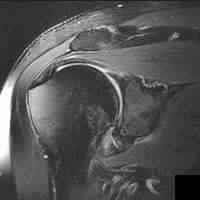

A 29-year-old elite volleyball player presents with insidious onset of shoulder weakness. Physical examination reveals isolated atrophy of the infraspinatus fossa with normal bulk of the supraspinatus. Weakness is noted in external rotation. An MRI demonstrates a paralabral cyst. Where is the cyst most likely located, and what is the typical associated labral pathology?

Explanation